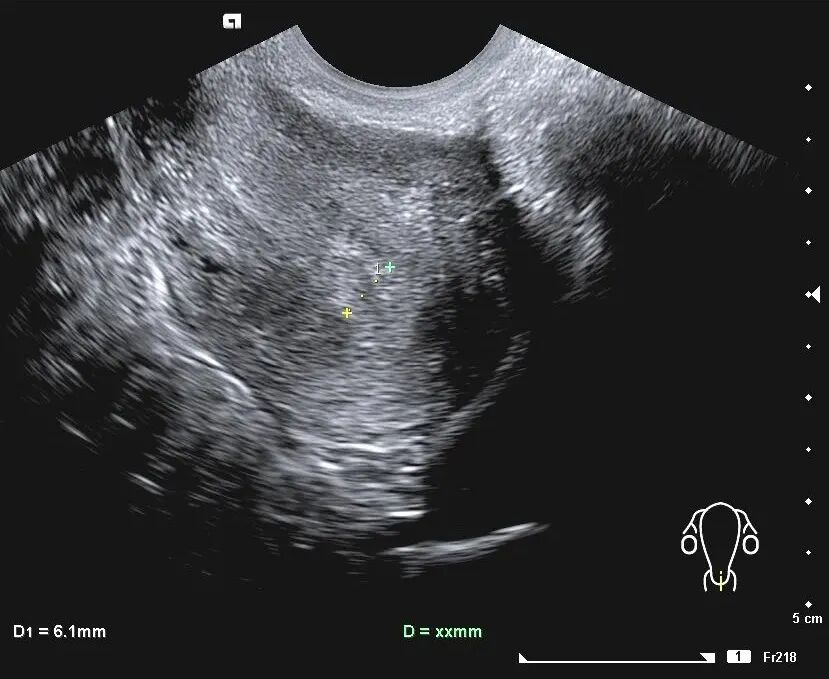

① 子宫内膜厚度

子宫内膜厚度是评价子宫内膜发育最简单、最常用的指标。

一般认为正常子宫内膜种植窗口期厚度约在9-11mm之间为最佳。

内膜<7mm时,妊娠率显著下降,< 6mm几乎没有妊娠的可能。但临床,极少数时候能看到4~5mm,也成功分娩的病例。

过厚的子宫内膜也被认为不利于胚胎着床,>14mm时,妊娠率也下降。